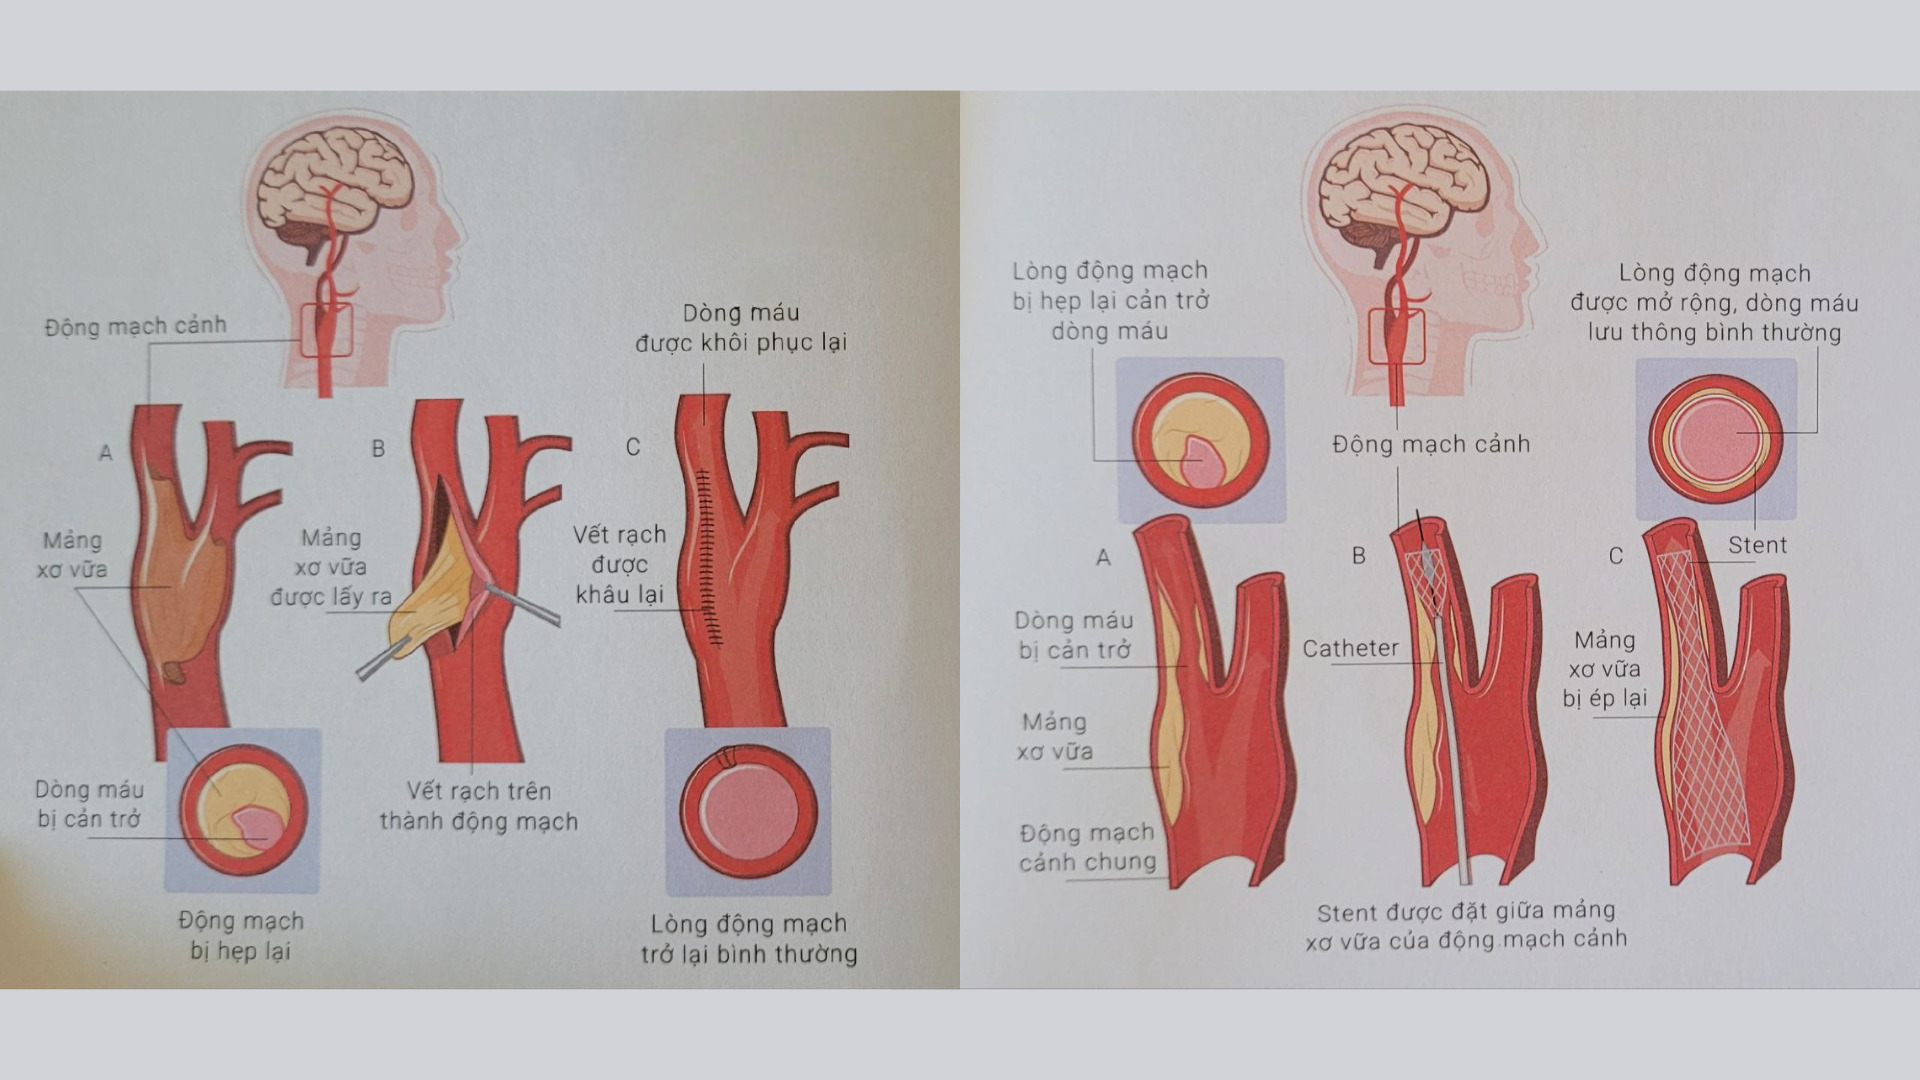

Các phương pháp điều trị khác trong điều trị Đột quỵ não

Bên cạnh các phương pháp phổ biến trong điều trị đột quỵ não, có một số phương pháp điều trị khác vẫn được áp dụng trong điều trị và mang lại hiệu quả.